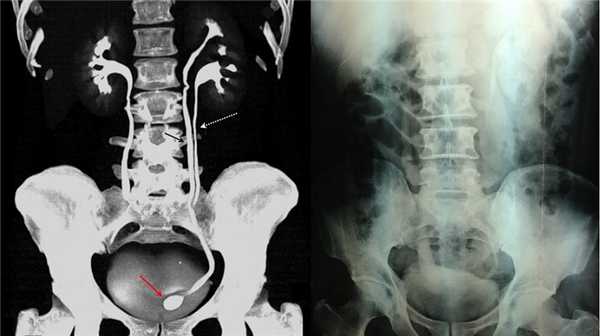

В марте 2002 г. в связи с эпизодом лейкоцитурии лечился у нефролога; при контрольном УЗИ впервые диагностированы изменения в мочевом пузыре и паравезикально слева. При повторном УЗИ выявлено (рис. 1а): правая почка увеличена в размерах (длина 12,7см; толщина паренхимы 1,6 см); чашечно-лоханочная система не расширена. Левая почка отсутствует. Стенки мочевого пузыря не изменены; в просвете слева определяется округлое образование 3,5 x 4,6 x 5,0 см с неоднородным содержимым (объем около 40 мл). Заключение: аплазия левой почки; уретероцеле слева.

а) Эхограмма.

б) Компьютерная томограмма.

в) Схема КТ.

Компьютерная томография (КТ): в проекции устья левого мочеточника и на фоне мочевого пузыря слева определяется дополнительная тень 3,1 x 4,0 x 4,0 см с четкими контурами и плотной стенкой. Мочеточник выше устья расширен до 1 см. Заключение: КТ-картина уретероцеле слева, уретерэктазия слева (рис. 1 б, в).

Рисунок. КТ-урография (1) показывает неполное удвоение ЧЛС слева: два мочеточника соединяются на входе в таз и единым мочеточником вступают в мочевой пузырь; внутрипузырная часть мочеточника расширена (красная стрелка) — уретероцеле. Уретероцеле хорошо видно на рентгенограммах (2) при экскреторной урографии: правый мочеточник расширен на всем протяжении, дистальный отдел кистозно расширен — «голова кобры».

Рисунок. Уретероцеле (стрелка) на УЗИ и КТ.